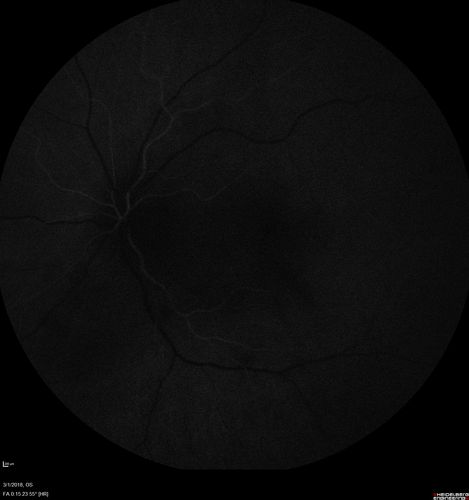

Neuroretinitis and Multifocal Retinitis

62 year old female with vision loss in the left eye to 20/160. Positive Bartonellas IgG. Vision recovered in 2 months. She was treated with Oral Erythromycin BID for 2 weeks.

Cat Scratch - Neuroretinitis - Multifocal Retinitis